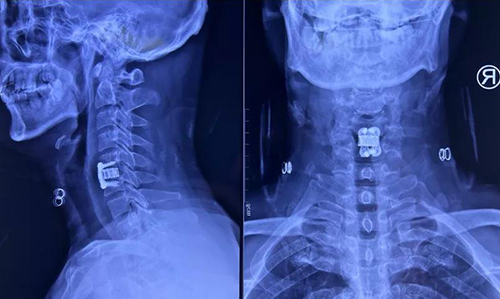

颈椎病例为49岁男性患者,主诉“双下肢走路不稳2月余,加重1月”。查体发现患者颈椎曲度变直并局部后凸。颈椎MRI显示C3/4、C5/6、C6/7椎间盘突出并椎管狭窄,C5/6水平脊髓变性。诊断为脊髓型颈椎病,颈椎间盘突出症。

该患者颈椎曲度变直并局部存在后凸畸形,通常这种颈椎融合手术应用不同规格的PEEK材料椎间融合器,术中椎间压配不良,术后植骨融合效果不确切。丰荣杰主任医师详细制定治疗策略,决定为患者进行显微镜辅助下颈椎前路减压植骨融合内固定术。通过使用3D打印钛合金椎间融合器,使融合器与椎板紧密解剖型贴附,增加了骨接触面积,能够获得即刻稳定。这种多微孔的结构可使自体骨直接长入,避免大量异体骨的使用,同时可有效纠正后凸畸形,从而实现在患者正常颈椎生理曲度下的完美融合。

术前X线

术后X线